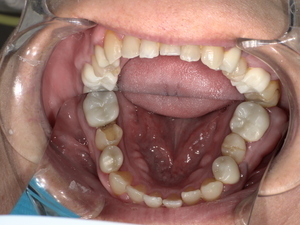

診察の結果、脱落した詰め物の周囲だけでなく、隣接する歯との適合性も著しく低下していました。

二次虫歯(再発虫歯)の進行: 詰め物と歯の隙間から菌が入り込み、内部で虫歯が広がっていました。

歯周病リスクの増加: 段差がある箇所にプラーク(歯垢)が溜まりやすく、歯茎の炎症を引き起こしていました。

噛み合わせの不調: 詰め物が欠けた状態で放置されていたため、反対側の歯に負担がかかっていました。

このまま「その場しのぎの補修」を繰り返しても、数年後にまた再発する可能性が高いと判断し、「精度」「耐久性」「審美性」のすべてを満たすジルコニアセラミッククラウンをご提案しました。

Before:白い詰め物がとれて、見た目も清潔感に欠ける状態。

After: セラミックで修復され、天然歯のように自然な白さと透明感がある美しい歯の状態。どこが治療箇所か分からないほど自然な白さへ。